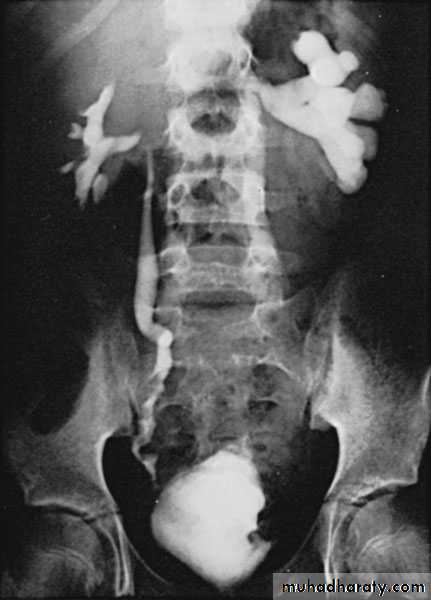

Postcaval (Retrocaval) ureter (Preureteral Vena Cava )

The right ureter pass behind the inferior vena cavaThis might causes obstruction

It is a vascular abnormality

Incidence: about 1 in 1500

Although it is congenital, most patients present at 3rd or 4th decade.

Diagnosis: IVU